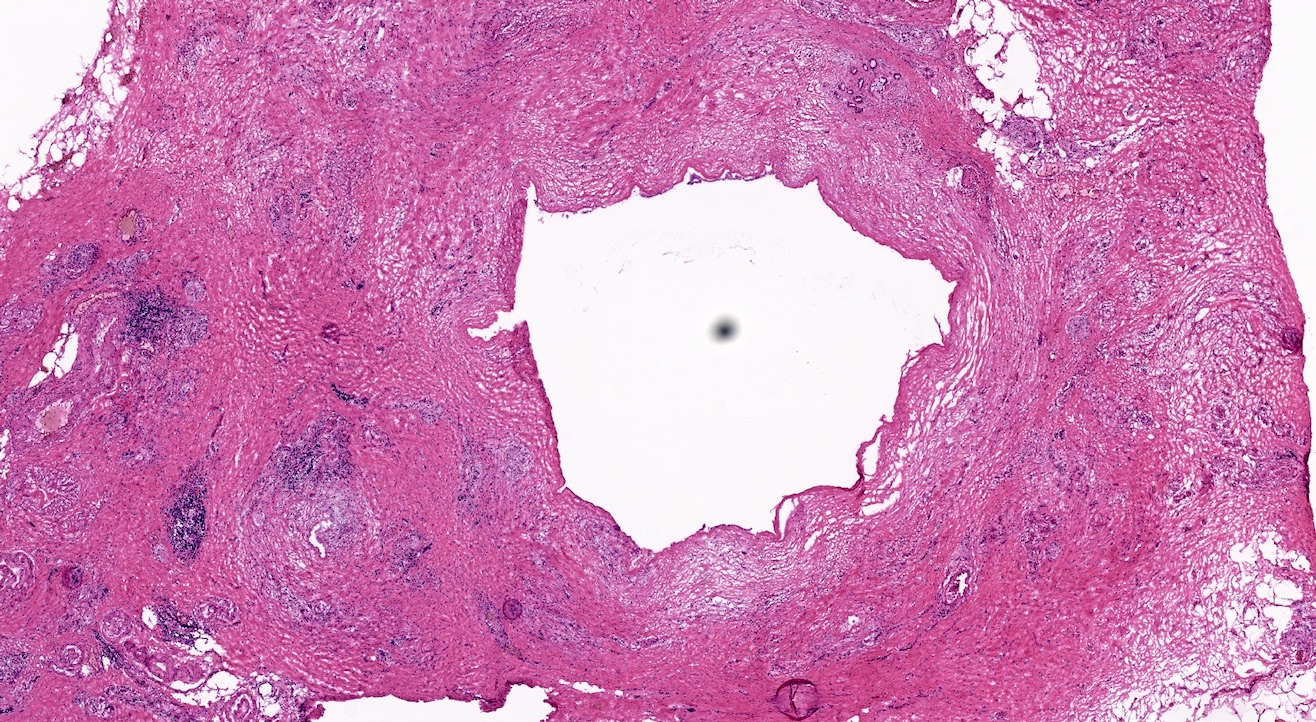

Microscopic (histologic) description

- Triad of cardinal features: fibrosis, loss of acinar tissue, duct changes (Pancreatology 2020;20:586)

- Fibrosis is initially perilobular; during disease progression, it involves the pancreatic lobular units, eventually replacing the acinar parenchyma (so called intralobular fibrosis)

- Acinar tissue may be replaced by fibrosis or fatty tissue; the latter process (lipomatous atrophy) is more frequently seen in hereditary pancreatitis (Pathologica 2020;112:197)

- Loss of acinar tissue predates that of pancreatic islets, which are often seen isolated in fibrosis or fatty tissue in advanced cases

- Ductal changes include distortion of ductal profiles, ectasia, presence of intraluminal concretions of amorphous material (so called protein plugs), squamous metaplasia, intraductal calcification

- Foci of low and high grade pancreatic intraepithelial neoplasia (PanIN) may be encountered

- Foci of periductal chronic inflammation and fat necrosis represent a common finding

- Pseudocysts lined by granulation tissue are common in alcoholic chronic pancreatitis

Microscopic (histologic) images